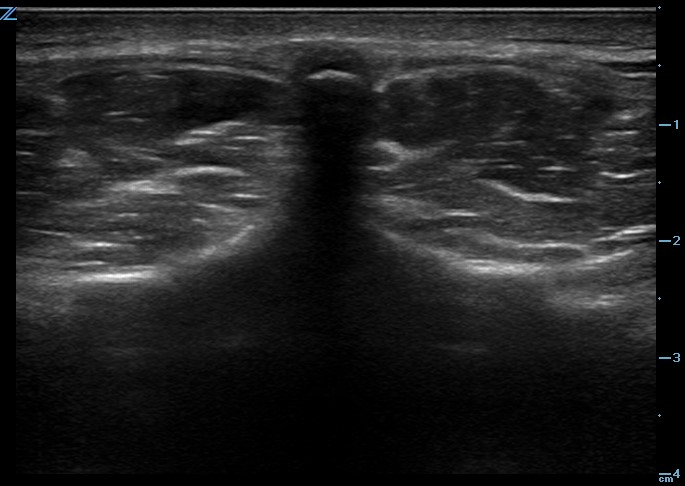

One recommended approach is to start with the probe in transverse position at the level of the sacrum and scan superiorly, sequentially identifying the spinous processes of L5, L4, L3, and L2. In the transverse orientation, spinous processes are seen as small, hyperechoic marks with dense vertical shadowing (Figure 1). With the probe centered over a spinous process, the operator uses a clean towel to wipe off excess gel, and a skin marker to place a vertical hash mark above and below the midline of the probe (Figure 2). Next, the probe is placed in longitudinal orientation over the same spinous processes, with the indicator toward the patient’s head. In this view, spinous processes will appear as wider, hyperechoic areas with distal shadowing (Figure 3). When two or more spinous processes are simultaneously visualized, the space between them is the area available for needle insertion. The skin is marked again, this time with horizontal hash marks extending outward from the midline of the probe (Figure 4).

Figure 1. Ultrasound image of spinous process in transverse plane.